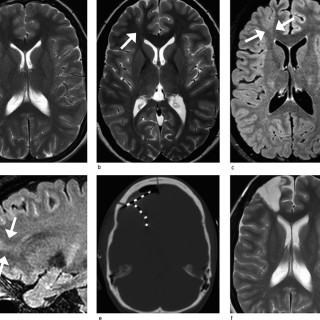

Downs syndrom er det hyppigst forekommende kromosomavviket hos mennesker, og i 2010 ble det født 69 levende barn med Downs syndrom i Norge (1,1 av 1 000 levende fødte) (1). Syndromet skyldes trisomi av hele eller en del av kromosom 21 i alle eller deler av kroppens celler og er assosiert med mental retardasjon, medfødt hjertefeil, gastrointestinale forandringer, redusert nevromuskulær tonus, utviklingsavvik i hode, hals og luftveier, karakteristiske ansiktstrekk og fysiske karakteristika, endrede audiovestibulære og visuelle funksjoner samt økt forekomst av flere sykdomstilstander (2, 3)...